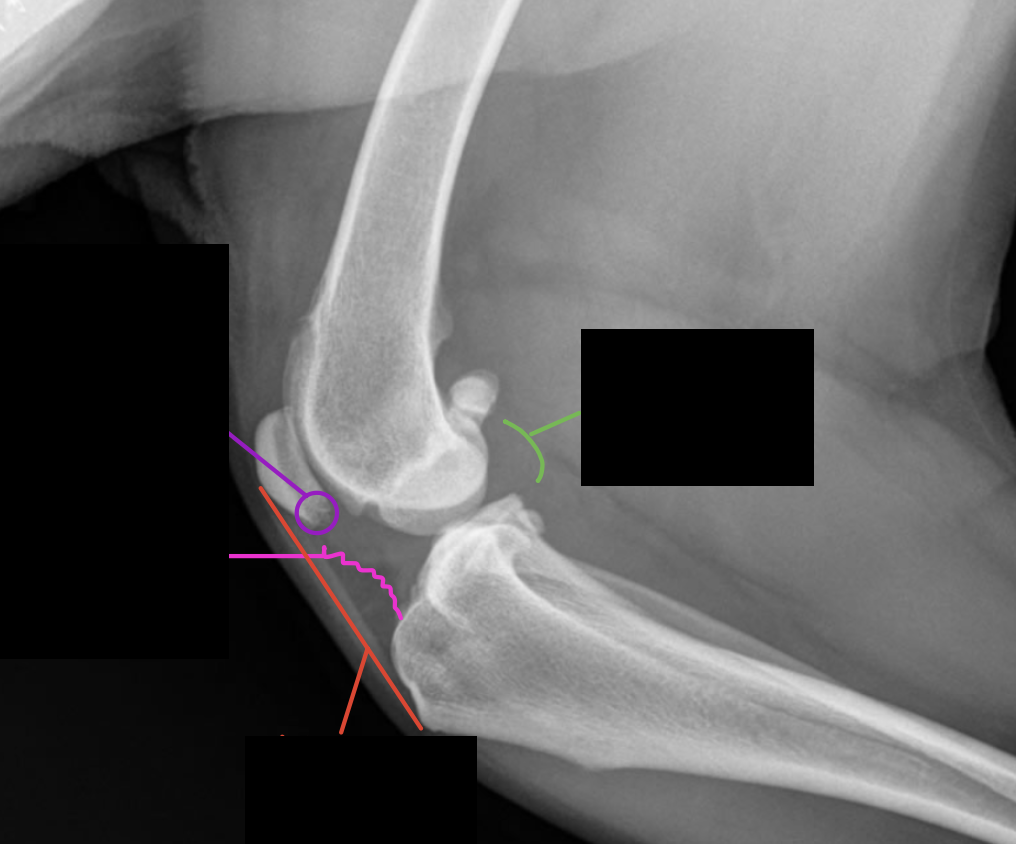

Label the structures

A = patella

B = distal femur

C = fabellae

D = tibia

E = fibula